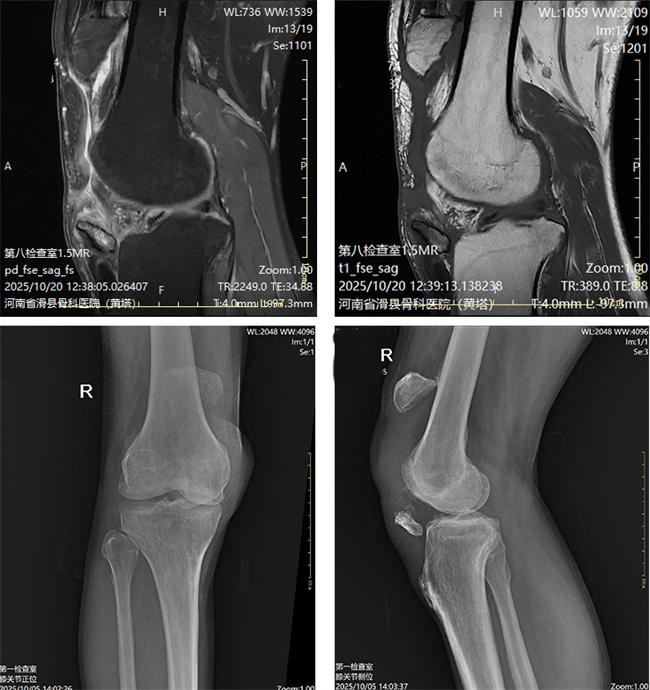

一、患者李某某,男,51岁,患者右膝部疼痛肿胀5个月,活动后疼痛明显,活动受限。为求进一步治疗,来到我院请专家会诊,通过各位专家会诊查体、查看影像资料并细致认真的分析后,建议:先行伊里扎洛夫架子固定牵引,择期行陈旧性髌骨骨折切复内固定术。